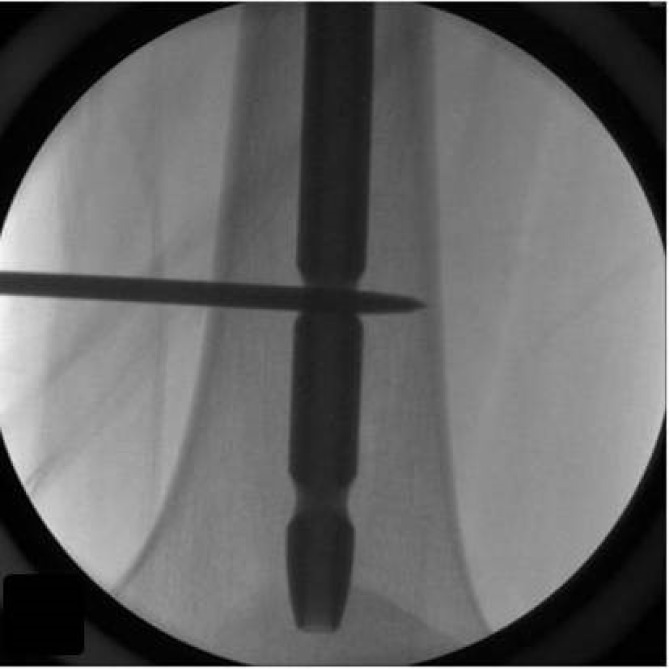

目的:准确定位远端钉孔和放置远端联锁螺钉是髓内钉的挑战。本研究提出了一种使用Steinmann销直接置入远端锁定螺钉的技术,无需重新定位销或钻头。方法:采用18个锯骨股骨模型和髓内钉。一名第一年住院医师在每个模型上创建了两个远端锁定孔,采用传统的徒手技术和一种新的方法,在图像增强下使用Steinmann销和锤子。这些技术基于三个参数进行评估:(1)创建远端锁定孔所需的时间,从针定位在孔中心的那一刻开始测量,直到远端皮质穿过联锁孔;(二)用个人伽马辐射剂量计估算的辐射剂量(单位:毫雷姆/小时);(3)失败次数,定义为在近皮层和远皮层上造成一个以上的洞。结果:与传统方法相比,新方法的放射剂量更低(P=0.0268),失败次数更少(P=0.0367)。此外,与传统方法相比,使用新技术建立远端孔所需的时间更短(P=0.0217)。结论:采用Steinmann销锤制作远端联锁孔准确、高效、经济。

Objectives: Accurately targeting distal nail holes and placing distal interlocking screws pose challenges during intramedullary nailing. This study proposes a straightforward technique for distal locking screw insertion using a Steinmann pin, eliminating the need to reposition the pin or drill bit. Methods: We utilized 18 Sawbones femur models and intramedullary femur nails. A first-year resident created two distal locking holes on each model, employing both the conventional freehand technique and a novel method involving a Steinmann pin and hammer under image intensification. These techniques were evaluated based on three parameters: (1) the time required to create distal locking holes, measured from the moment the pin was positioned at the center of the hole until the far cortex was drilled through the interlocking hole; (2) the radiation dose (in mrem/h), as estimated with a personal gamma radiation dosimeter; and (3) the number of failures, defined as the creation of more than one hole in the near and far cortex. Results: The new technique was associated with a lower radiation dose (P=0.0268) and fewer failures (P=0.0367) than the conventional approach. Additionally, the time required to establish distal holes was shorter using the new technique compared to the conventional method (P=0.0217). Conclusion: The creation of distal interlocking holes with a Steinmann pin and hammer is accurate, efficient, and cost-effective.